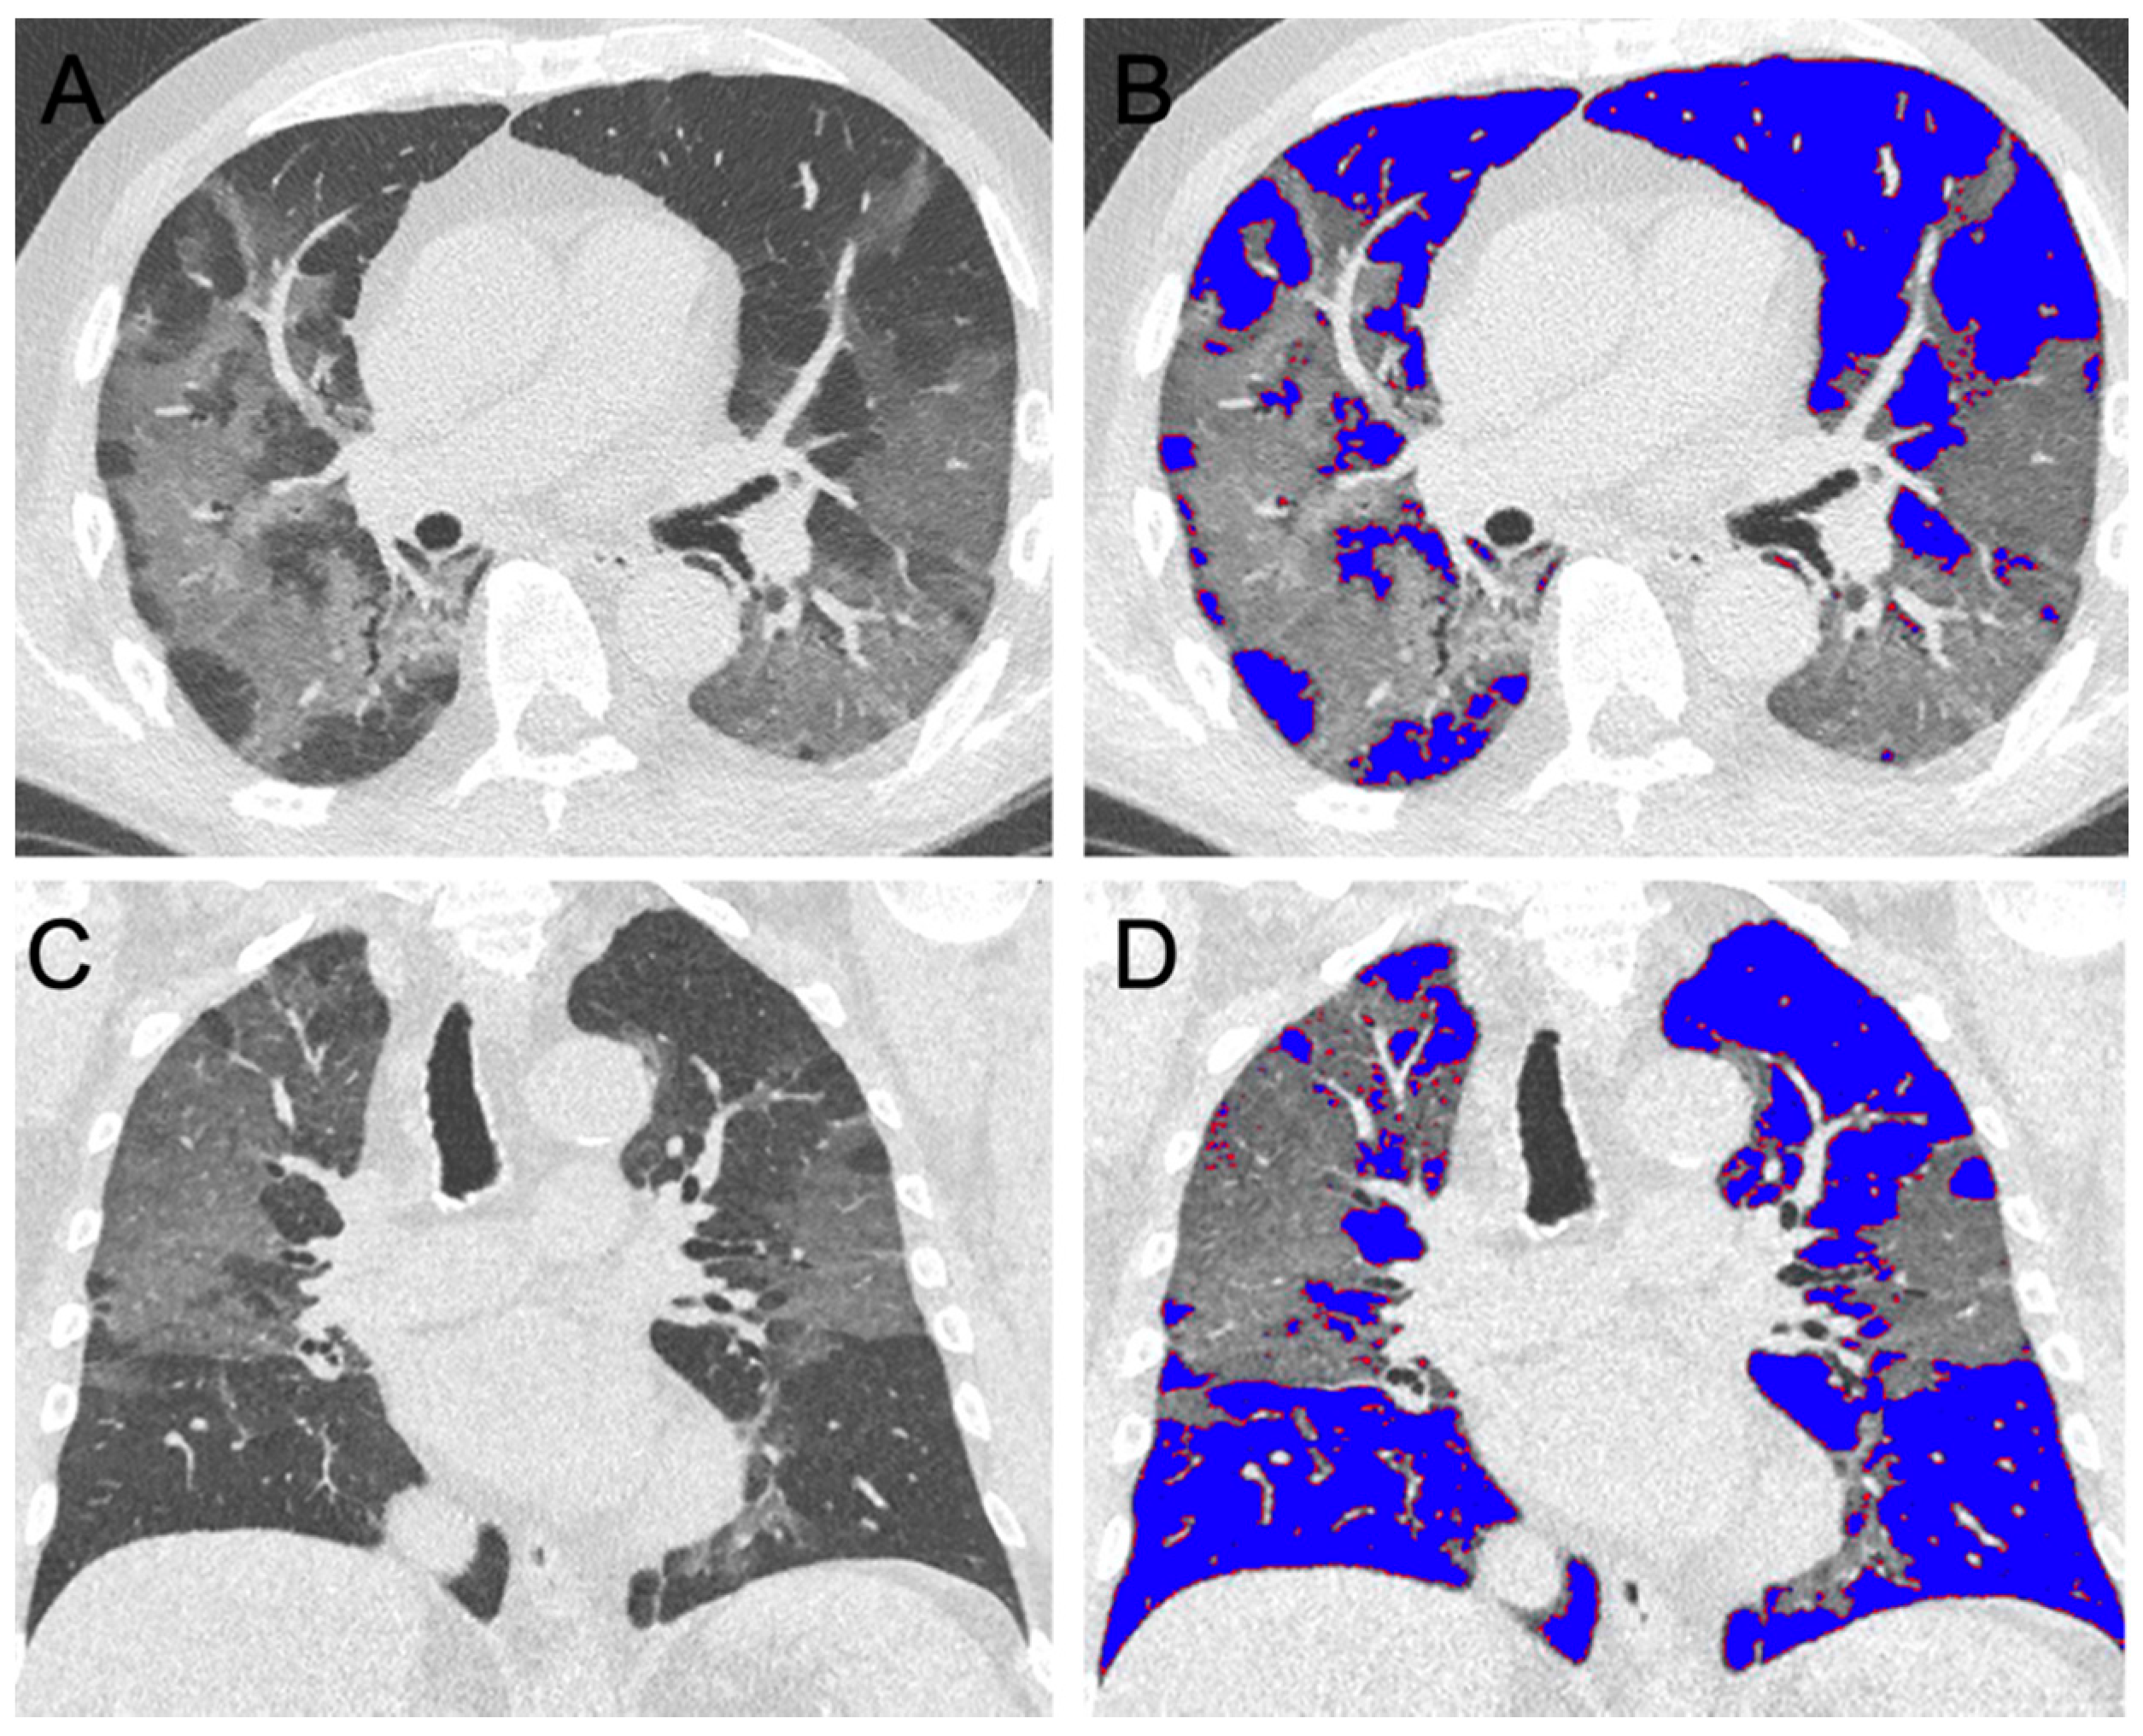

2.4. Semi-Automated Lung Parenchyma Volume Quantification